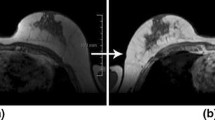

In imaging studies, saline (salt water) and gas (such as air) are also employed as contrast materials. Ultrasound imaging exams, particularly those of the heart, have used microbubbles and microspheres. Blood perfusion in organs is assessed using contrast-enhanced ultrasonography with microbubbles [17], thrombosis, such as in myocardial infarction, cardiac anomalies, liver and kidney tumours, inflammatory activity in inflammatory bowel illness and reaction to chemotherapy treatment (Fig. 9.1).

Fig. 9.1 Illustration example for non-contrast and Gd Contrast MRI images.